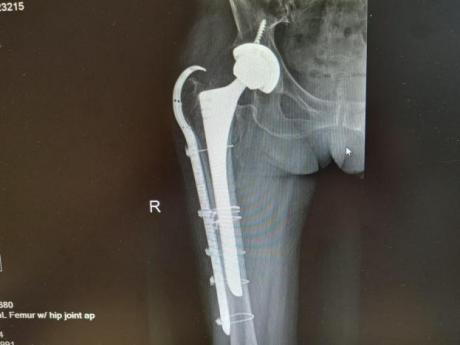

12月17日,贵州航天医院第88次晨读会由我院骨一科主任、副主任医师陈明勇作学术交流,他以“肱骨近端骨折并肩关节脱位的手术治疗”为题,全面讲解了该损伤的手术策略、术中血供保护理念及内侧支撑重建技术等内容,并通过多个典型病例图文资料分享了从损伤机制分析、手术步骤实施到术后随访评估的完整过程与关键细节,为临床处理此类复杂骨折提供了较为全面的技术参考,有助于在手术规划中结合个体情况开展针对性治疗。 贵州航天医院 骨科专家简介 陈明勇 骨一科主任,副主任医师 临床擅长:从事创伤骨科工作约20年,对骨缺损、骨不连、骨肿瘤、肢体畸形等的肢体矫形重建及功能重建,慢性化脓性骨髓炎的根治治疗、糖尿病足的保肢治疗、快速康复理念(ERAS)下的老年骨折的诊治,四肢复杂骨折的诊治,四肢骨折等微创手术治疗具有丰富的临床经验。 2004年毕业于遵义医学院临床专业,曾在中国人民解放军总医院、广西医科大学第一附属医院、上海第六人民医院骨科进修。中国中西医结合学会骨伤科专业委员会横向骨搬移治疗糖尿病足及微血管网再生学组首届委员,遵义市医学会创伤分会常务委员。 瞿 晖 骨科党支部书记,骨二科主任,副主任医师 临床擅长:对骨科的常见病、关节外科、脊柱外科及运动医学疾病的诊治具有丰富的临床经验,熟练掌握骨科手术操作技术。 毕业于遵义医学院临床医学系,2005年前往广州中山大学第一附院骨显微医学部进修学习,2011年前往成都华西医院进修学习,并多次在省内外学习骨科相关知识,是中华医学会骨科分会会员。 赵小锋 中共党员,骨二科副主任,副主任医师 临床擅长:从事骨科临床工作11年,对骨科常见病、多发病诊疗有较为丰富的临床经验,擅长脊柱相关疾病诊断及治疗,尤其是颈、腰、腿疼痛疾病诊断及治疗,擅长胸腰椎骨折微创经皮穿刺内固定术、经皮穿刺椎体成形术、经皮穿刺脊柱内镜下腰椎间盘摘除术、单纯开创腰椎间盘摘除术、腰椎滑脱复位椎间植骨椎融合内固定术、腰椎管狭窄减压融合内固定术及人工髋、膝关节置换术等。 2012年毕业于遵义医学院外科学专业硕士研究生,2019年参加“遵义市115医学人才精英计划”于上海交通大学第一附属医院培训学习,2023年于北京大学第三人民医院脊柱外科进修学习,曾获得遵义市优秀医师荣誉称号。 遵义市手外科第一届委员,遵义市医学会创伤分会第一届委员,遵义市医学会创伤分会第二届委员,贵州省康复医学会第三届脊柱脊髓专业会委员,遵义市医学会烧伤与整形外科学分会委员,发表论文5篇,其中国家级核心期刊1篇,SCI论文1篇,主持市级课题1项并结题,参与市级课题2项。 赵兴东 骨科主任医师 临床擅长:擅长骨科的常见病及各种创伤、四肢骨折创伤修复、骨感染、手足疾病的诊治和手足体表畸形的矫形整复,熟练掌握骨科四肢骨病及创伤的手术操作技术,尤其在四肢关节复杂性损伤、手足外伤、组织缺损创面、难治创面的皮瓣修复方面及平足、高弓足矫形方面及四肢慢性疼痛诊治、康复方面具有丰富的临床经验。 硕士研究生,毕业于遵义医学院临床外科系,2015年前往山东省立医院手足外科进修学习;遵义市医学分会创伤分会第一、二届委员,遵义市手外科医学会第二委届员会常务委员;在省级及省级以上期刊发表文章9篇,参编著作2部,参与主持并完成市级课题1项,参与市级课题2项、省级课题1项。 张艳金 中共党员,骨科副主任医师 临床擅长:从事骨外科工作16年,对复合伤、多发伤的救治、四肢骨干骨折、关节周围骨折、骨肿瘤、骨髓炎等诊治具有丰富的临床经验。 中共党员,硕士研究生,2006年本科毕业于山西医科大学第二临床医学院,2011年研究生毕业于北京军区总医院;在“老年COPD患者合并髋部骨折的诊治”国际合作课题组研究两年,在老年髋部骨折的诊治方面具有丰富的经验,并发表论文6篇;主持遵义市级课题1项,承担遵义医科大学的临床教学工作,获得遵义医科大学优秀带教老师荣誉。编撰有《骨科疾病诊疗精粹》一书,开展2项新技术,编撰地方规范《务川自治县创伤骨科常见疾病诊疗规范》一书。 张俊凯 骨科副主任医师 临床擅长:从事骨科临床工作28年,对创伤骨折、骨感染、骨缺损、骨不连等外科诊治,四肢骨折的微创手术治疗,四肢复杂骨折(如关节内粉碎性骨折、多发骨折等)的损伤控制及手术治疗等具有丰富的临床经验。 1995年毕业于遵义医学院临床专业,2009年前往复旦大学附属医院骨科进修1年。 卢懿明 中共党员,骨科副主任医师 临床擅长:从事骨科工作18年,对创伤骨折、四肢骨折的微创手术治疗、四肢复杂骨折(如关节内粉碎性骨折、多发骨折等)的损伤控制及手术治疗,尤其是髋部骨折的PFNA等微创技术,踝关节骨折、膝关节周围骨折的Mipo微创技术等具有丰富的临床经验,开展了4项新技术,发明6项新型专利技术。 2005年毕业于遵义医学院临床专业,2017年,前往南方医科大学第三附属医院骨科进修半年,回院后运用Mipo技术对骨干骨折及干骺端骨折的治疗技术,同时积极开展骨盆骨折、髋臼骨折腹直肌外侧切口的应用;发表了多篇专业论文,经常参与省内外学术交流会授课,获得医院荣誉称号多个。 邬夏荣 骨科副主任医师 临床擅长:从事骨科工作16年,对四肢复杂骨折、骨肿瘤的诊治,尤其是足踝创伤、慢性踝关节损伤、平足症等诊疗具有丰富的临床经验。 2006年毕业于遵义医科大学临床医学专业,曾在陆军军医大学西南医院进修学习,发表多篇骨科学术论文。 余德怀 中共党员,骨科副主任医师 临床擅长:从事骨科工作10余年,对运动医学、骨关节、脊柱外科常见病、多发病的诊治具有丰富的临床经验。 硕士研究生,2011年毕业于遵义医学院临床医学专业,曾前往遵义医科大学附属医院运动医学专业进修学习;是贵州省医学会运动医学分会青年委员,西部关节镜联盟委员;发表多篇骨科学术论文。 冯 乾 骨科副主任医师 临床擅长:从事骨科工作近20年,熟练掌握骨科多发病及常见病的诊治,尤其对脊柱退变性疾病的诊断及治疗具有丰富的临床经验,主要研究脊柱微创相关治疗方式,能熟练开展椎间孔镜及UBE。 曾前往北京大学第三医院进修学习疼痛及椎间孔镜、首都医科大学友谊医院专业进修脊柱内镜;是贵州省康复医学会第三届脊柱脊髓专业委员会委员;发明专利3项、发表脊柱外科专业论文多篇。 贵州航天医院骨科简介 基本情况 贵州航天医院(原3417医院)骨科组建于1968年,前身是以创伤和断肢(断指)再植闻名于世的上海市第六人民医院骨科,中国断肢(断指)再植的奠基者、中科院院士陈仲伟等专家莅临科室指导医疗和教学,并在70年代开展了贵州省首例断肢(断指)再植手术。组建50余年来,诊治患者已逾百万,挽救了无数的伤病员,成为了保障遵义地区人民群众健康的重要支撑。 经过几代人的不懈努力,今天的骨科,已由创伤骨科发展至骨病、骨肿瘤、骨结核等领域,现有脊柱外科、关节外科、四肢创伤、手足外科四个亚专科,成为了集医疗、教学、科研于一体的综合学科,是贵州省临床重点专科、遵义市临床重点专科、遵义市骨科临床医学中心、遵义市基层骨科专科联盟理事长单位。 科室目前开放床位110张,共有医护人员50余人,副高级以上专家18人,硕士研究生15人。拥有一流骨科医疗设备多台,每年不定期选派优秀技术骨干到全国各大知名医学院校进修、学习、参观、交流,并邀请国内、国外知名专家教授来院进行交流、指导,通过不断引进国内外先进的诊疗技术,科室医疗技术水平稳步提升,为广大人民群众提供了优质的医疗服务。 专科特色 骨一科 (一)骨缺损、骨不连的肢体与功能重建 胫骨横向骨搬移技术治疗糖尿病足: (二)慢性骨髓炎的根治治疗 (三)肢体缺血性疾病如糖尿病足、脉管炎的保肢治疗 (四)皮瓣修复 (五)复杂创伤的治疗 (六)老年髋部骨折及小儿骨折快速手术 老年髋部骨折: 骨二科 (一)胸腰椎骨折微创经皮椎弓根螺钉固定术 (二)老年性骨质疏松性患者腰椎滑脱脊柱内固定术(骨水泥螺钉) (三)V形双通道脊柱内镜技术(VBE)腰椎融合术治疗腰椎退行性疾病 (四)老年性骨质疏松性骨折(PVP/PKP)术 (五)人工髋关节置换术 (六)双侧股骨头坏死人工全髋关节置换 (七)右侧全髋置换术后假体周围骨折翻修 (八)人工膝关节置换术 (九)人工膝关节假体松动翻修 (十)关节镜技术 传统手术切口 关节镜技术切口 诊疗范围 骨一科 1.四肢创伤、矫形。 2.手、足踝外科。 骨二科 end